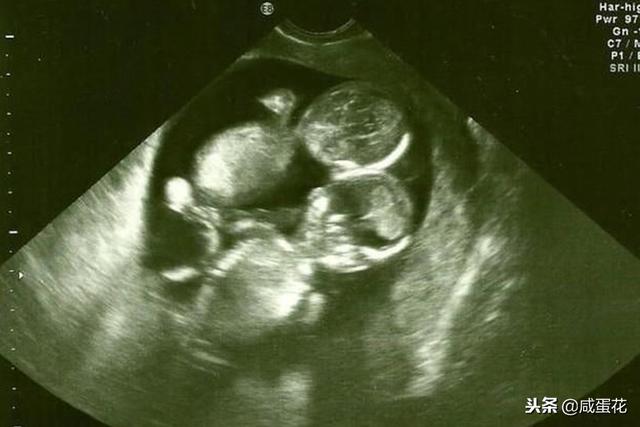

做到这几点,想不怀上双胞胎都难!

据相关调查显示 , 有近七成的备孕家庭希望可以怀上双胞胎 。 一方面同时生下两个宝宝可以让妈妈少一次怀孕生子的辛苦经历 。 另一方面 , 生两个宝宝 , 两个可以一起陪伴着彼此长大 , 成长的过程中会少很多孤单 。 但是 , 很多宝妈不知道自己可以为怀上双胞胎做哪些努力 , 甚至有很多人就因此听天由命了 , 能怀上双胞胎全是靠天赏饭 。 今天小编要告诉各位宝妈的是 , 只要做到以下的几点 , 怀上双胞胎的几率就会大大上升哦 。